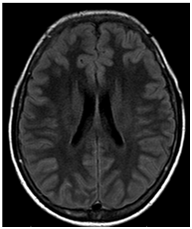

Two days after aminophylline was started, there was improvement of areas with high DWI signal. Four days later, the patient recovered movements on the face and upper limbs. In the two- week follow-up, demonstrated areas of high signal in T2 in correspondence previous areas of change of signal in DWI. (Figures 6‒8).

Figure 7 (FLAIR) now it is possible to identify correspondently high signal FLAIR images.

Figure 8 (FLAIR) now it is possible to identify correspondently high signal FLAIR images.

The MR imaging findings consists of increased signal intensity on DWI with correlated hypointensity on the ADC map are indicative diminished random water motion, usually associated with irreversible cytotoxic injury. However, it can be identified in acute MTX neurotoxicity related to cytotoxic edema and is not necessarily associated with irreversible cell death as the proposed mechanism. After recovery, DWI findings are usually normal, but T2 and/or FLAIR (Fluid-attenuated inversion recovery) may show residual abnormalities until 3weeks. Reversibility of markedly decreased in apparent diffusion coeficient (ADC) values without a clinically apparent permanent deficit is in striking contrast with findings in acute ischemia.13

The case here presented showed the expected evolution of a subacute transient encephalopathy with a stroke-like manifestation. It is common adverse effect of MTX medication and it tends to resolve spontaneously within few days. However, once it is diagnosed, aminophylline plays a special role on reversing and preventing from further MTX- toxicity related symptoms. MRI is fundamental on the diagnosis, showing focal white matter lesions which are firstly seen in DWI and within days, these areas vanishes in DWI and appears in T2 images. As these focal areas disappear in DWI, there is a correlation with clinical symptoms improvement.